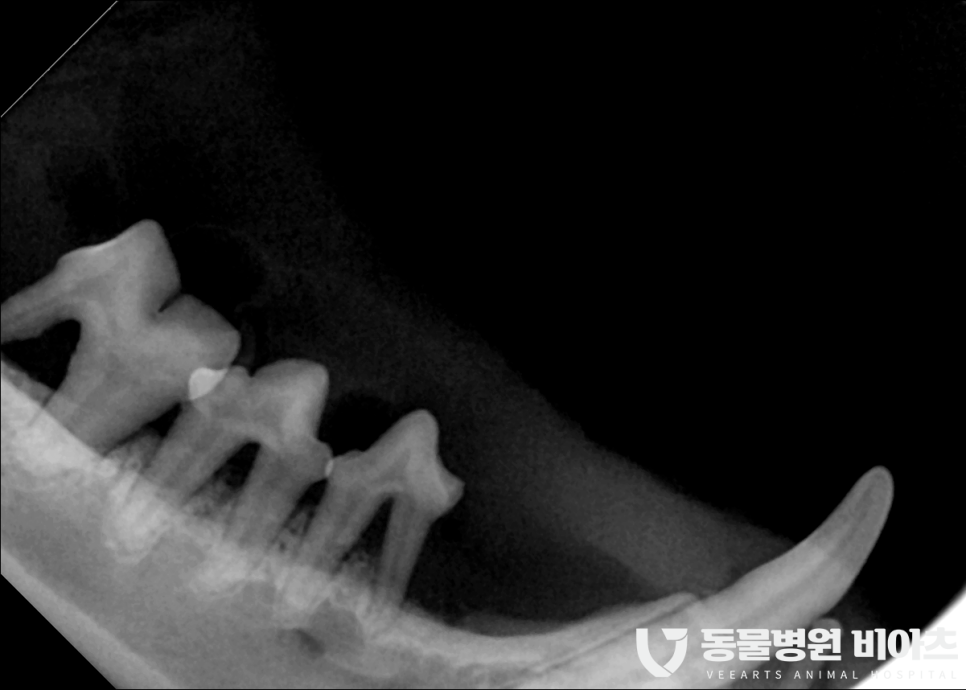

수술 전 치과 엑스레이를 통해

최소 10컷 이상의 촬영을 합니다.

치과 엑스레이는 보통 발치 전 발치 후

모두 찍습니다.

엑스레이 촬영을 통해 뿌리까지 완벽히 제거가

되었는지 확인을 해야 하기 때문입니다.

그냥 사진만 봐도

상태가..

많이 안 좋습니다..